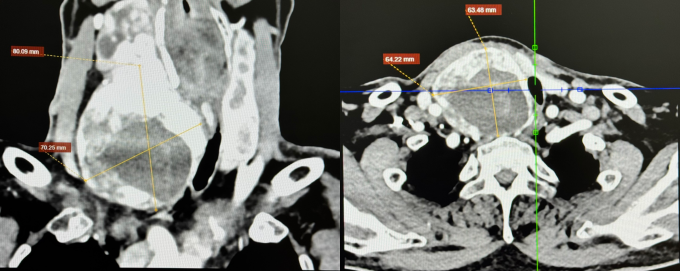

Ông Kỳ, 67 tuổi, có tiền sử tăng huyết áp, rối loạn lipid máu, suy thận mạn giai đoạn 3. ThS.BS.CKI Phạm Ngọc Minh Thủy, khoa Ngoại Tim mạch, Trung tâm Tim mạch, Bệnh viện Đa khoa Tâm Anh TP HCM, cho biết thùy phải tuyến giáp của ông Kỳ kích thước 68x68x121 mm. Bướu giáp thòng xuống hõm ức, đẩy khí quản, thực quản sang trái, khiến lòng khí quản còn 9 mm (trong khi đường kính bình thường khoảng 20 mm).

Ảnh chụp CT cho thấy bướu giáp kích thước lớn, chèn ép khí quản. Ảnh: Bệnh viện Đa khoa Tâm Anh

Theo ThS.BS Trần Thúc Khang, Phó khoa Ngoại Tim mạch, Trung tâm Tim mạch, đường thở hẹp hơn 55% cho thấy mức độ chèn ép nặng, thực quản nằm sát ngay sau khí quản bị đẩy lệch làm cản trở thức ăn lưu thông xuống dạ dày. Người bệnh có nguy cơ bị khàn tiếng mạn tính, khó thở cấp tính, nhuyễn sụn khí quản (vòng sụn khí quản yếu đi, mất khả năng đàn hồi), ngưng thở khi ngủ, sặc thức ăn vào đường thở… nếu không điều trị kịp thời.